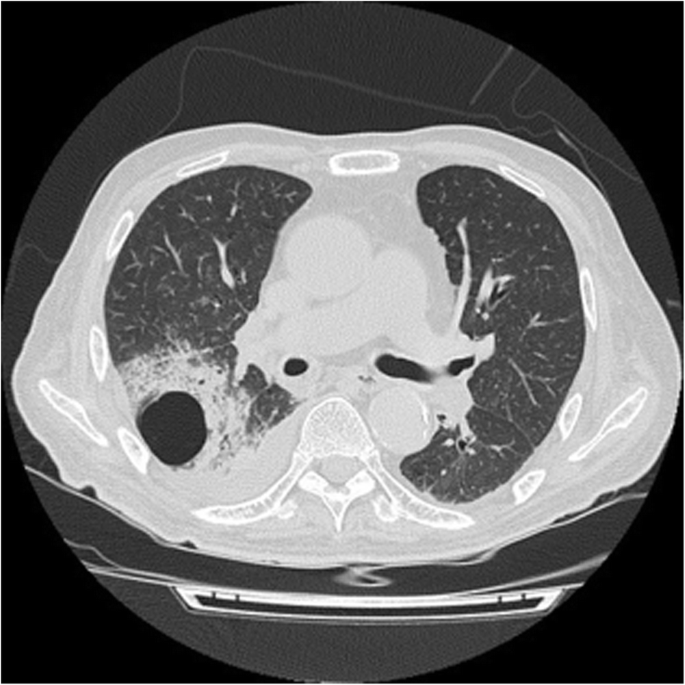

A 72-year-old Japanese man with hypertension and chronic kidney disease due to type 2 diabetes mellitus was referred to our medical center with worsening of the serum creatinine (sCr) level for 2 weeks. He had a baseline sCr of 1.1 mg/dL. The patient never smoked or had no family history of kidney or rheumatic disease. On examination, his respiratory rate was 24 breaths per minute, his heart rate was 73 bpm, his blood pressure was 125/64 mmHg, he had a saturation of 83% in room air, and his body temperature was 38.6 °C. Physical examination was remarkable for labored breathing using respiratory accessory muscles, bilateral coarse crackles, and pretibial pitting edema. There was no rash or purpuric skin lesion. Notable laboratory findings included severe anemia (hemoglobin level, 5.9 g/dL) and a markedly decreased kidney function (blood urea nitrogen (BUN), 182 mg/dL; sCr, 27.3 mg/dL; estimated glomerular filtration rate (eGFR) [6], 1 ml/min/1.73 m2). The immunoglobulin (Ig) levels were normal (IgM, 80 mg/dL; IgA, 196 mg/dL), except for elevation of IgG (1958 mg/dL). Urinalysis showed proteinuria (4.8 g/gCr) with microscopic hematuria (> 100 erythrocytes per high-power field) and a few red blood cell casts. Plain computed tomography showed bilateral pleural effusion and normal-sized kidneys. Antinuclear antibodies and proteinase 3 (PR3) and myeloperoxidase (MPO) antineutrophil cytoplasm antibodies (ANCA) were negative. Anti-GBM antibody was 476 units/mL. PR3-ANCA, MPO-ANCA, and anti-GBM antibody were measured using enzyme-linked immunosorbent assay method. Anti-GBM disease was confirmed by renal biopsy, which showed 10 glomeruli, seven of them had cellular crescent formation (Fig. 1) and three had global sclerosis. A moderate interstitial infiltration composed of monocytes and neutrophils was observed. Immunofluorescence microscopy showed linear staining for IgG along with the GBM (Fig. 2). Along with oral prednisolone (40 mg/day), double-filtration plasmapheresis (DFPP) using human albumin (5%) as the replacement material was initiated. The patient’s anti-GBM antibody decreased from 476 to 18 units/mL with twelve sessions of DFPP, but he underwent hemodialysis because his renal function did not recover. One month after completion of DFPP, however, the patient died from lung abscess (Fig. 3) caused by Pseudomonas aeruginosa.